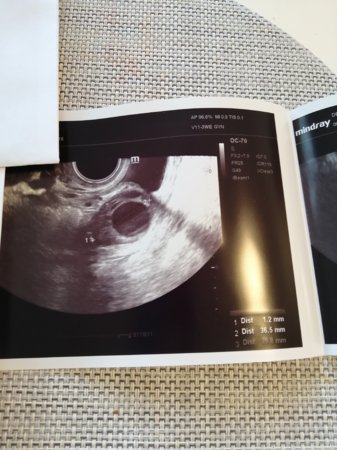

Kyllä mä alan vähitellen uskomaan tähän :Heartred Ehkä meille tuleekin jouluvauva :smiley-angelic001

Nyt Dpo11. Oireita tuntuu olevan melkein vähemmän kuin edellisessä kierrossa jolloin olin olevinani ihan varma raskaudesta :hilarious: Pissalla tosin pitää käydä noin 100 kertaa päivässä, ja kohdussa on kevyitä tuntemuksia (ei varsinaista jomotusta, mut sellaista pientä fiilistä).

Tottakai on kauhu siitä, et mitä jos taas menee kesken tai tulee jotain muuta ongelmaa... Mutta yritän olla antamatta pelolle valtaa, ja nauttia tästä hetkestä.

Kiitos kaikille ihanille naisille tässä ketjussa, oon saanut teidän keskusteluista mielettömästi vertaistukea ja tietoa lapsentekohommista! Nyt vasta tajuaa, miten hölmön naivi sitä oli silloin joskus, kun tätä hommaa aloitettiin... Ja silloin edellisessä raskaudessa, piti jotenkin asiaa ehkä liiankin itsestäänselvänä. Kuvaavaa ehkä se, et silloin tein yhden (1) raskaustestin ja luotin siihen varhaisultraan asti. Nyt on jo tähän dpo 11 mennessä mennyt yhteensä 6 testiä kolmen päivän aikana :hilarious: Terveisin anonyymi tikkuunpissaaja-addikti :rolleyes:

Hyvältä näyttää, onnea! Itsekin tekisin miljoona testiä :grin